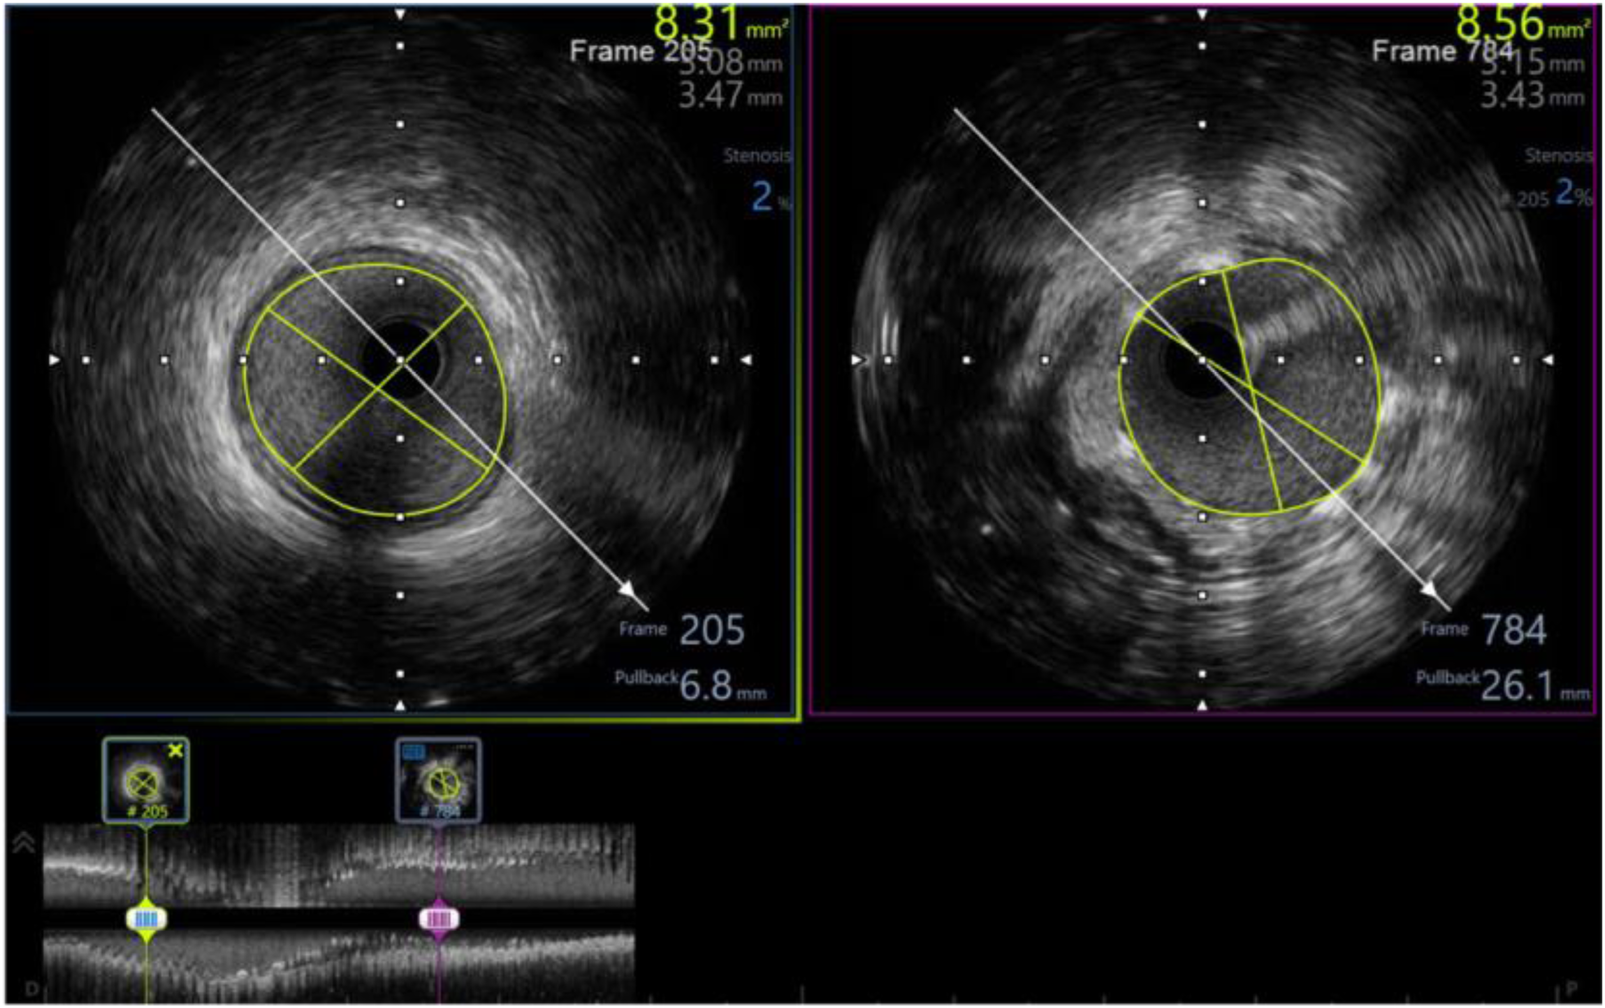

In our study, 98.3% of patients received intravascular ultrasound prior to implantation to evaluate the lesion characteristics and to select the appropriate scaffold size, as well as an intravascular ultrasound after the intervention to evaluate the effectiveness and success rate of the procedure. All of the patients received post-intervention balloon dilation. The efforts to follow the same process have helped the procedure to achieve a successful intervention rate of 100% (Table 6). Figures 3–5 displayed IVUS imaging of a patient who underwent Magmaris implantation using IVUS.

Figure 5

Post-procedure IVUS of the same patient (from Figures 3, 4) showed minimum stent area of 8.56 mm2 (# 102% distal reference lumen area) with well apposition, no tissue protrusion, and no edge dissection.